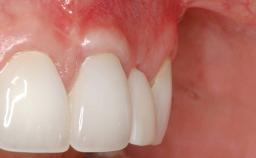

Implant Placement in the Esthetic Zone and Coverage of Multiple Gingival Recessions

This case illustrates use of a modified ‘tunnel’ technique, which has been shown to be highly effective in root coverage procedures. The tunnel technique is used to achieve soft-tissue augmentation across the anterior area, including the planned implant site, using collagen matrix as grafting material. The patient is a 47-year-old woman with high esthetic expectations. Her main concern was the appearance of the anterior teeth and their “elongation”.

Prosthesis Type FDP